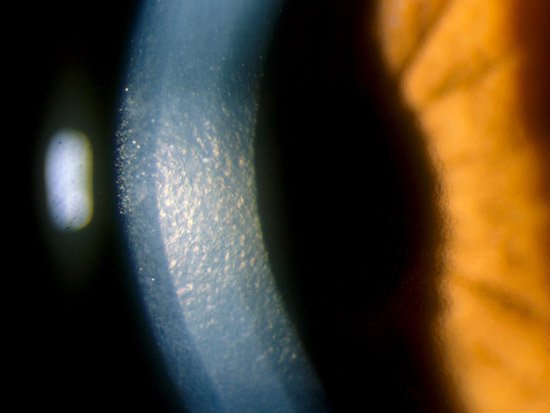

이때 각막모양이 Beaten bronze 혹은 Beaten metal 이라 하여,

두드린 놋쇠 혹은 두드린 금속과 같은 모양이라고 합니다.